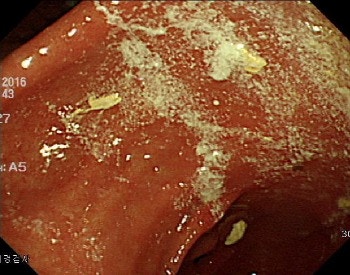

그래서 오늘은 내시경 전의 주의사항이나 특정 약 복용은 괜찮은지 등에 대해 이야기하고자 합니다.내시경 검사란?내시경으로 신체의 다양한 내강을 관찰, 검사함으로써 검사가 필요한 장기에 내시경을 삽입하고 기체나 액체로 내강을 부풀리면서 장기의 구조와 상태를 파악하는 검사 방법입니다.

수술로 몸을 절개하지 않아도 눈으로 조직의 병변을 확인할 수 있다는 장점이 있습니다.

내시경 검사로 단순한 염증성 질환부터 친정, 암, 용종 등 다양한 질환을 판단할 수 있습니다.